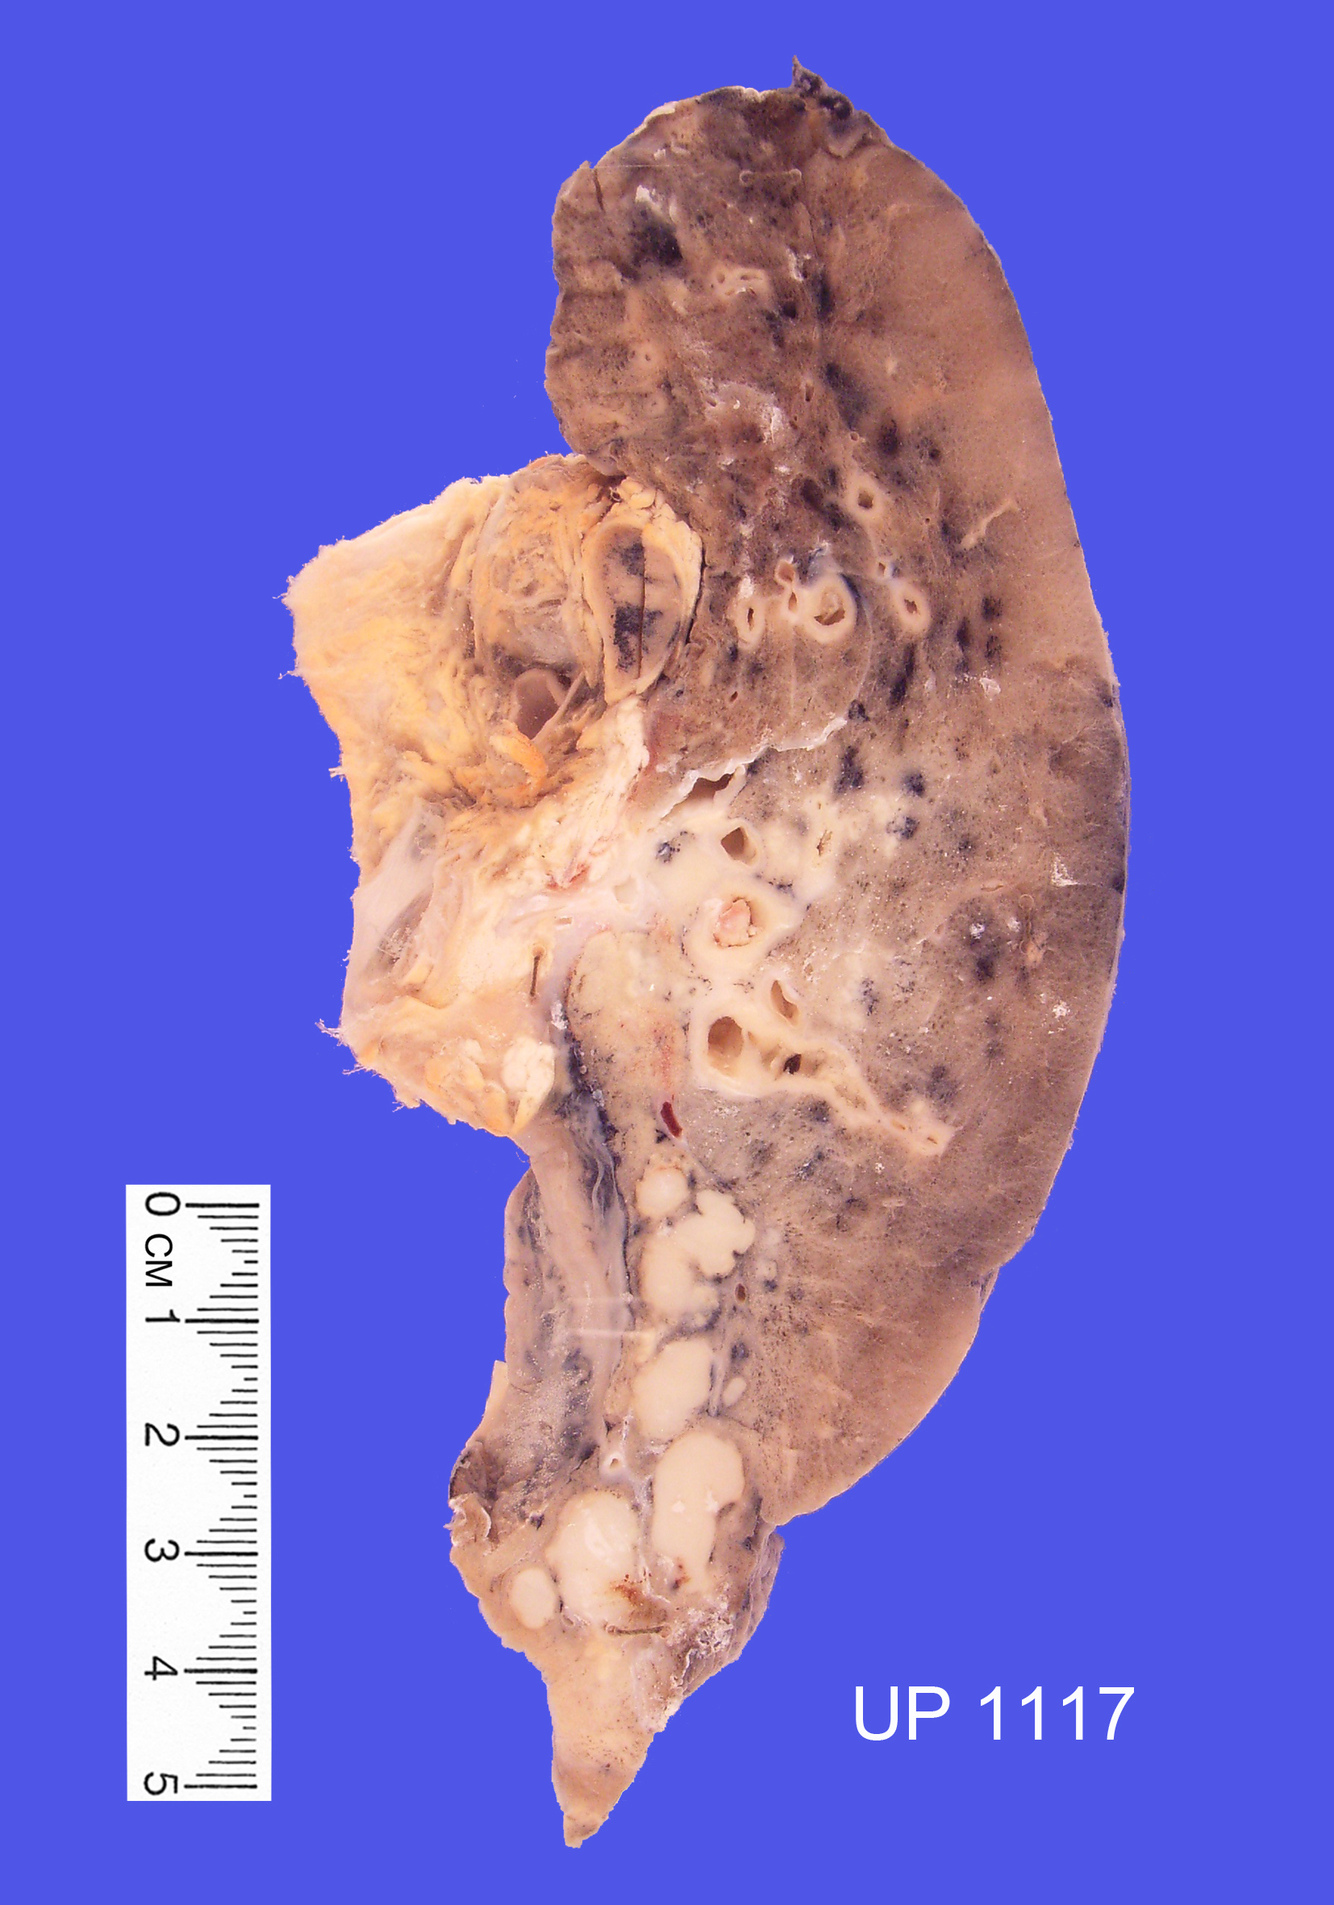

Specimen of left lung

Lung parenchyma shows honeycomb appearance, with large cyst-like spaces, particularly in upper lobe.

The lower lobe appears fibrotic

Usual Interstitial Pneumonia

UIP Micro?

Patchy Interstitial Fibrosis

Patchiness results from presence of early and late lesions: some showing inflammation, others showing collagen scar healing

Overall effect = destruction of lung parenchyma

Enlarged air-spaces with fibrous remodelling of airspace walls

Honeycomb lung formation - enlarged air spaces